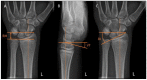

Osseous deformities in children arise due to progressive angular growth or complete physeal arrest. Clinical and radiological alignment measurements help to provide an impression of the deformity, which can be corrected using guided growth techniques. However, little is known about timing and techniques for the upper extremity. Treatment options for deformity correction include monitoring of the deformity, (hemi-)epiphysiodesis, physeal bar resection, and correction osteotomy. Treatment is dependent on the extent and location of the deformity, physeal involvement, presence of a physeal bar, patient age, and predicted length inequality at skeletal maturity. An accurate estimation of the projected limb or bone length inequality is crucial for optimal timing of the intervention. The Paley multiplier method remains the most accurate and simple method for calculating limb growth. While the multiplier method is accurate for calculating growth prior to the growth spurt, measuring peak height velocity (PHV) is superior to chronological age after the onset of the growth spurt. PHV is closely related to skeletal age in children. The Sauvegrain method of skeletal age assessment using elbow radiographs is possibly a simpler and more reliable method than the method by Greulich and Pyle using hand radiographs. PHV-derived multipliers need to be developed for the Sauvegrain method for a more accurate calculation of limb growth during the growth spurt. This paper provides a review of the current literature on the clinical and radiological evaluation of normal upper extremity alignment and aims to provide state-of-the-art directions on deformity evaluation, treatment options, and optimal timing of these options during growth.